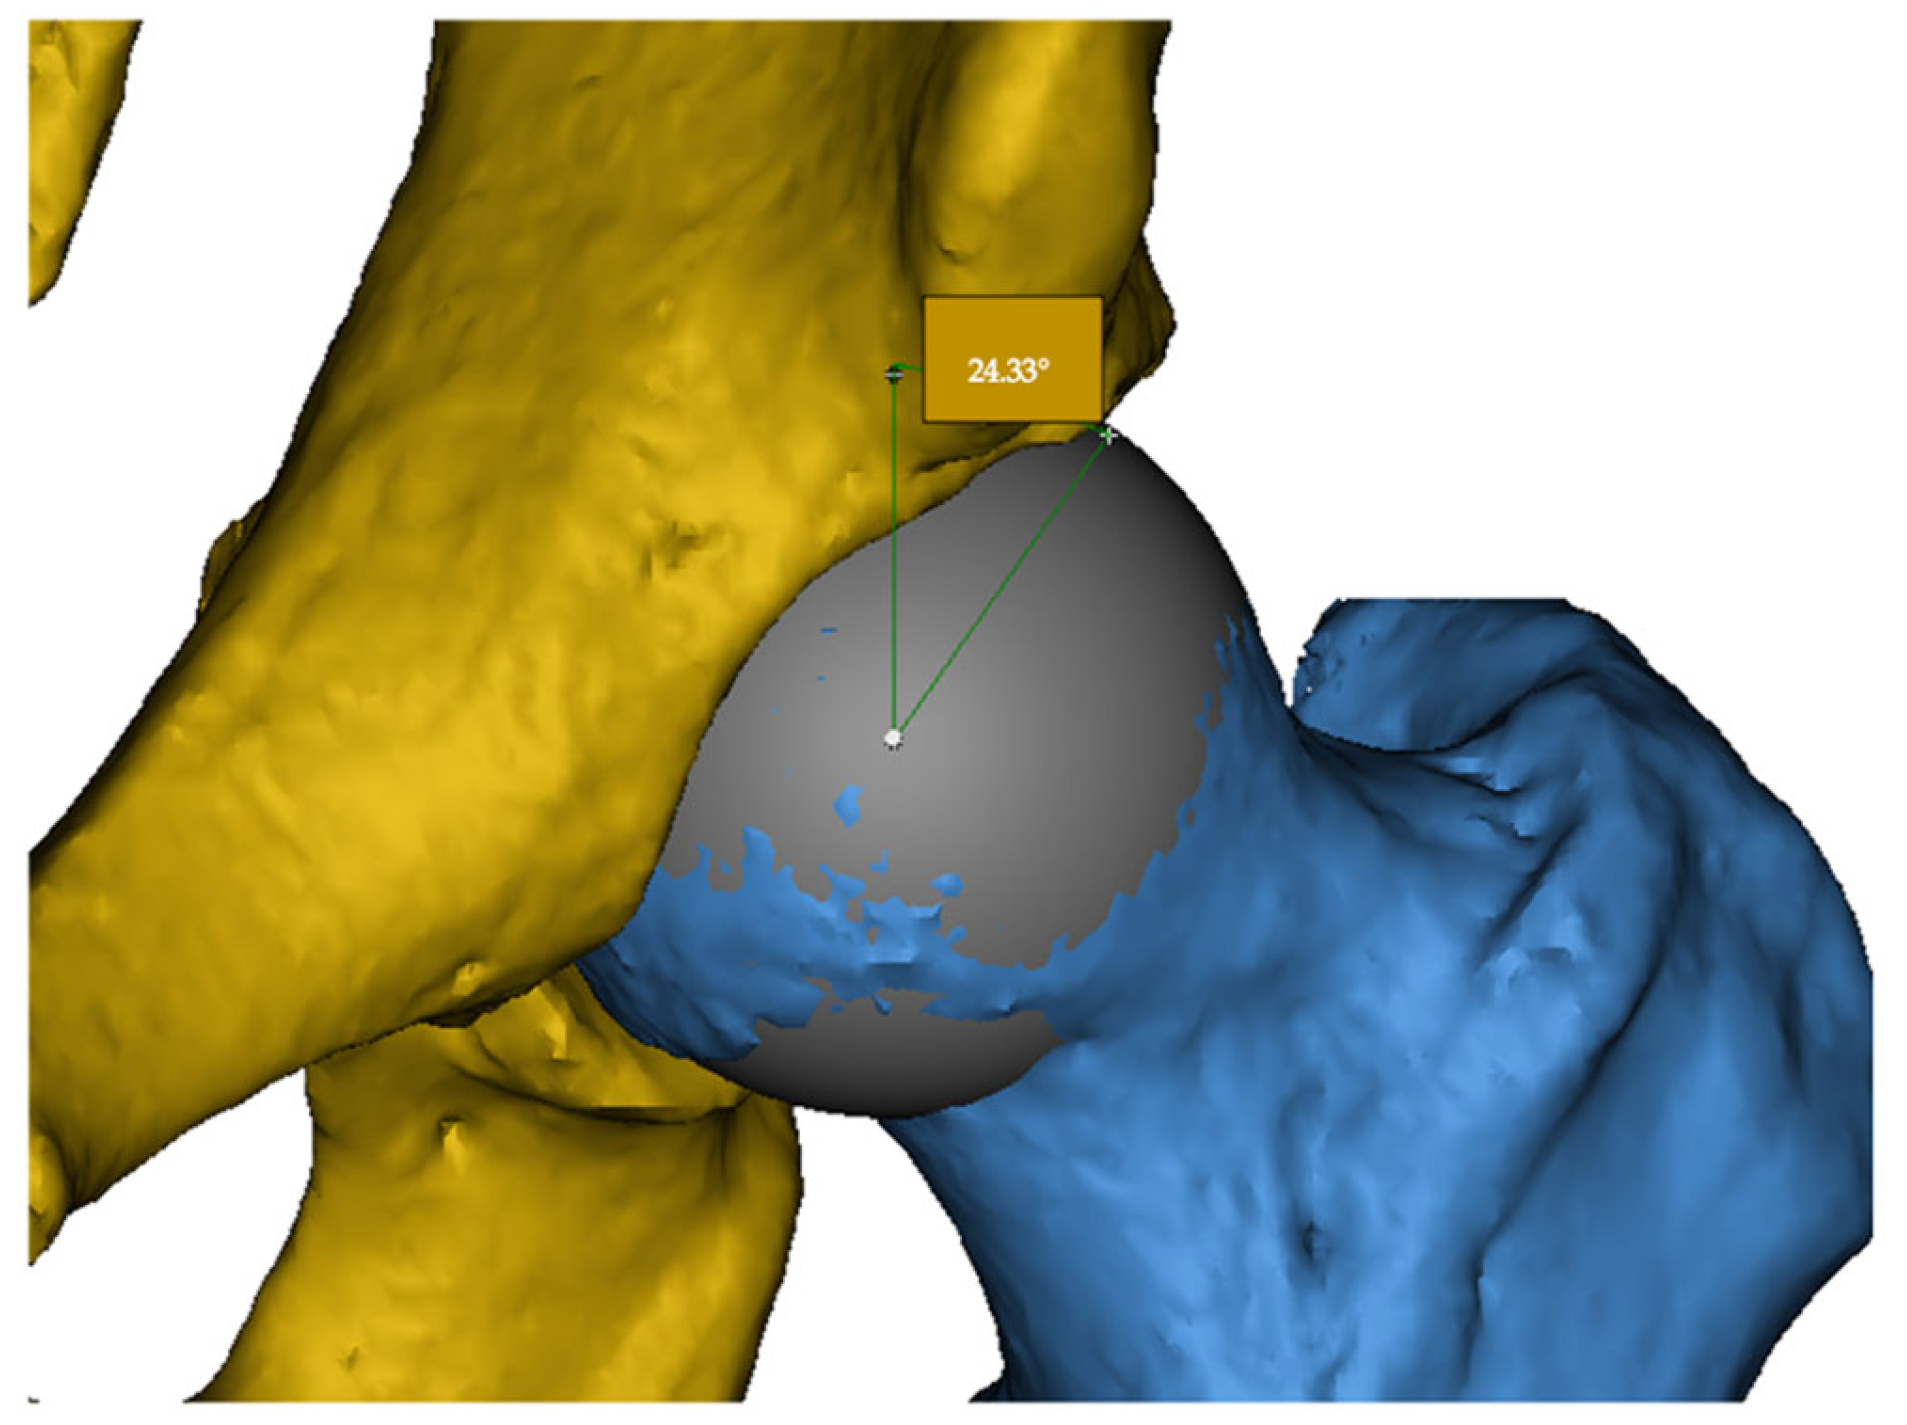

2.1.1. Lateral Center-Edge Angle (LCEA)

The LCEA is defined as the angle between a vertical line passing through the center of the femoral head and a line drawn from the center to the lateral edge of the acetabular roof. This angle quantifies the degree of acetabular coverage over the femoral head. Excessive LCEA values suggest pincer-type impingement, whereas low values may indicate acetabular dysplasia (Figure 1).

Figure 1. Measurement of the lateral center-edge angle (LCEA) on a 3D CT reconstruction. The acetabulum is shown in yellow and the femoral head in blue. The example demonstrates an LCEA of 24.33°.